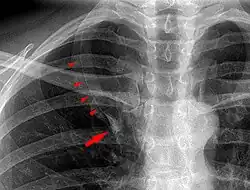

In human anatomy, an azygos lobe is a normal anatomical variation of the upper lobe of the right lung.[1] It is seen in 0.3% of the population.[2] Embryologically, it arises from an anomalous lateral course of the azygos vein,[3] in a pleural septum within the apical segment of the right upper lobe or in other words an azygos lobe is formed when the right posterior cardinal vein, one of the precursors of the azygos vein, fails to migrate over the apex of the lung and penetrates it instead, carrying along two pleural layers as the azygous fissure, that invaginates into the upper portion of the right upper lobe.[1]

An azygos lobe is usually an incidental finding on chest x-ray or CT scan. It is asymptomatic and not associated with any morbidity.[4][5] However, it can cause technical problems in thoracoscopic procedures.[6] The presence of the azygos lobe could alter the normal location of the superior vena cava or may be associated with other anomalies, including esophageal atresia or intrapulmonary right brachiocephalic veins.[7]